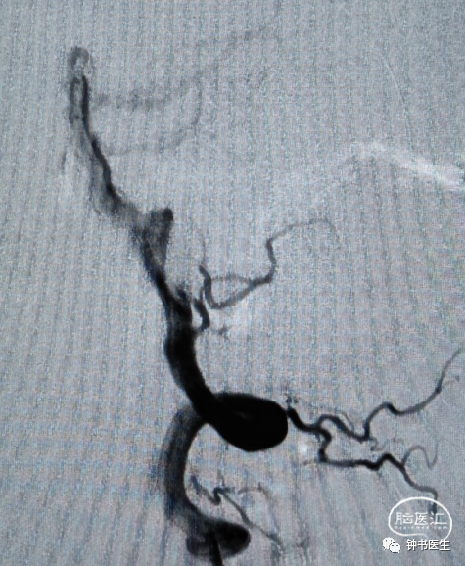

椎基底夹层动脉瘤:65Y M,脑干梗塞

术后患者无明显不适(TB 6.0X45)